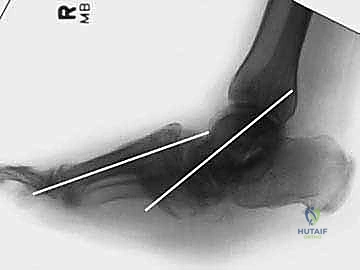

2. الأشعة السينية الحاملة للوزن (Weight-bearing X-rays): لتقييم الانهيار العظمي.

هذه هي الخطوة الأكثر دقة. يقوم الدكتور هطيف بإعادة العظام إلى وضعها التشريحي الطبيعي لاستعادة القوس الطولي للقدم، والتأكد من أن باطن القدم أصبح مسطحاً وقابلاً لتحمل الوزن مستقبلاً دون التسبب في تقرحات.

يتم استخدام أسلاك توجيهية (Guide Wires) يتم إدخالها تحت توجيه الأشعة السينية المباشرة (C-arm) من خلال عظام مشط القدم، مروراً بمفاصل منتصف القدم، وصولاً إلى عظام الرصغ (مثل العظم الزورقي أو الكاحل). بعد التأكد من المسار الصحيح، يتم استخدام مثقاب خاص، ثم تُدرج المسامير المحورية الصلبة (غالباً مسامير بقطر 6.5 مم أو 7.0 مم) لضغط المفاصل وتثبيتها بقوة هائلة.